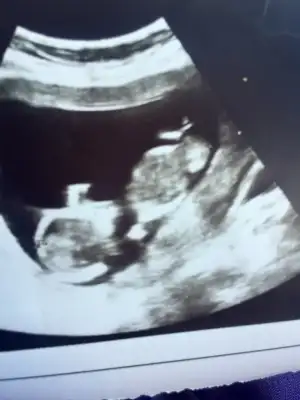

Hadi ya,hayırlısı olsun canım.yanılmışız demekki.kafa yapısı kız gibi duruyordu.çok istiyordun kıZın olmasını ama nasip böyleymiş canım Allah sağ Salim kucağına almayı nasip etsin

aynen öyleydi çok ağladım ama sağlıklı olsun da hayırlısı buymuş 🙂